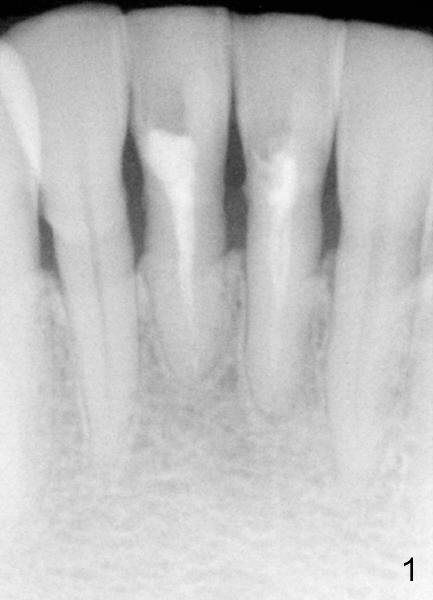

Two PAs were taken at different angulations (Fig.1,2 vs. 3,4).  The shortest M-D width of the tooth #24 is 3.16 mm (Fig.4 vs. 4.54 mm in Fig.2, probably close to the B-L width).

There is plenty of dimension in height.  What is the appropriate size of the implant?  How to handle the discrepancy of M-D and B-L widths?

Dear Dr. Borgner: Thanks for the advice again. The patient showed up this afternoon. The tooth (in fact #25 in Fig.5) is pretty badly broken down, but the patient is not ready for implant right now. Prefabricated post and temporary crown are provided. Fig.6 shows the longest post space that can be gained. The mesiodistal dimension of the tooth is 3 mm above gingiva clinically; the buccolingual 5 mm; the minimal dimension between #24 and 26 is 3.5 mm. There is plenty of height. The longest one piece tapered implant from Tatum Surgical is 17 mm. The appropriate implant should be 3x17 or 3.5 x17 if the proximal surfaces of #24,26 are to be trimmed further. This was done when the temporary crown was fabricated. Anyway, thanks for guidance.